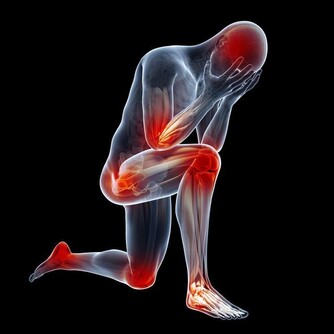

關節病是可以困擾老中青三代的常見的骨科疾病,其中,膝關節作為身體重要的支撐及活動結構,

因運動不當或隨著年紀變大,膝關節出現損傷的機率往往較其他關節更大。

組成膝關節的小夥伴有骨頭、軟骨、肌肉、韌帶和肌腱,構成膝關節的任何一個成分出了問題,都壞導致膝關節疼痛或不能行動。

2、關節病,什麼原因引起?

不分種族不分性別不分年齡,任何人都可能患上關節病。 關節病可以是膝關節直接受到衝擊或扭傷,也可以是關節骨和軟骨部分磨損、撕裂而引起。 炎症性關節病還可以由風濕性疾病引起,比如風濕性關節炎或系統性紅斑狼瘡,這些疾病導致的關節腫脹對關節的損傷是永久性的。